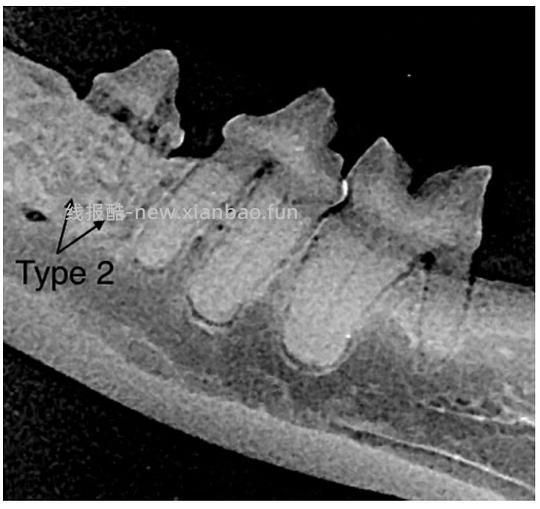

口腔内X光牙科片在诊断和确定治疗计划上起着重要作用。根据在影像学上表现出的特点,牙吸收可分为三种类型如下(图10)[1, 18]:

图*10(a)1型牙吸收(b)2型牙吸收(c)3型牙吸收[18]

Type2(T2): 对于具有2型吸收的牙齿,牙周韧带间隙至少在某些区域变窄或者消失,部分牙齿的射线不透性降低 - 图10(b)+图12

图12 下颌前臼齿2型吸收[1]